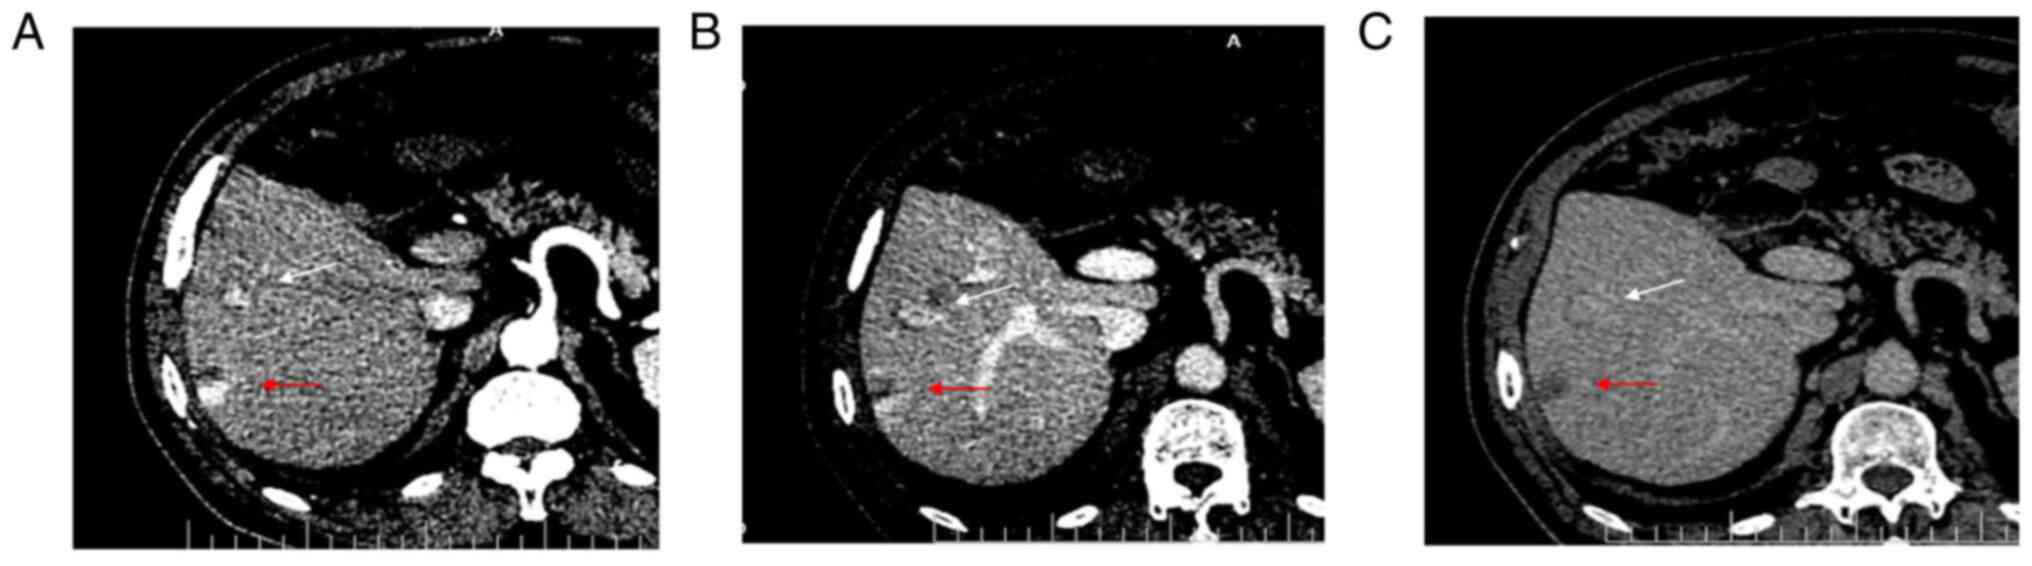

Imaging analysis of the malignant transformation of bile duct hamartomas in the liver: A case report and literature review

Bile duct hamartoma in the liver (LBDH) is relatively rare among the hepatic space‑occupying lesions that occur in adults, and the malignant transformation of LBDH is even rarer. In the present case report, a 63‑year‑old male was found to have two space‑occupying lesions in the right lobe of the liver upon ultrasound examination. Enhanced computed tomography (CT) suggested benign hepatic haemangioma, and contrast‑enhanced ultrasonography (CEUS) suggested well‑differentiated hepatocellular carcinoma. The final pathology results revealed the malignant transformation of LBDH into well‑differentiated intrahepatic cholangiocarcinoma. Improved recognition of this type of rare disease can be obtained by radiographic analysis of this case. These findings contribute to a better understanding of the enhanced development pattern of this disease on contrast‑enhanced CT, as well as on CEUS.